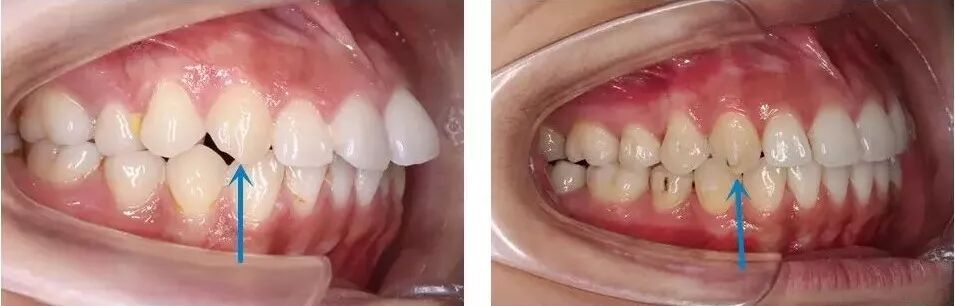

一个案例:

这个女生矫正前有一定的拥挤,并且伴有深覆盖。

仔细看侧面的口内,她的牙齿上牙咬合太往前了。所以矫正方案采用远移上颌磨牙,使咬合稳定(磨牙及尖牙中性关系),并排齐牙列。

前牙配合邻面去釉解除拥挤,原本“翘起来”的龅牙也完美内收了进去。